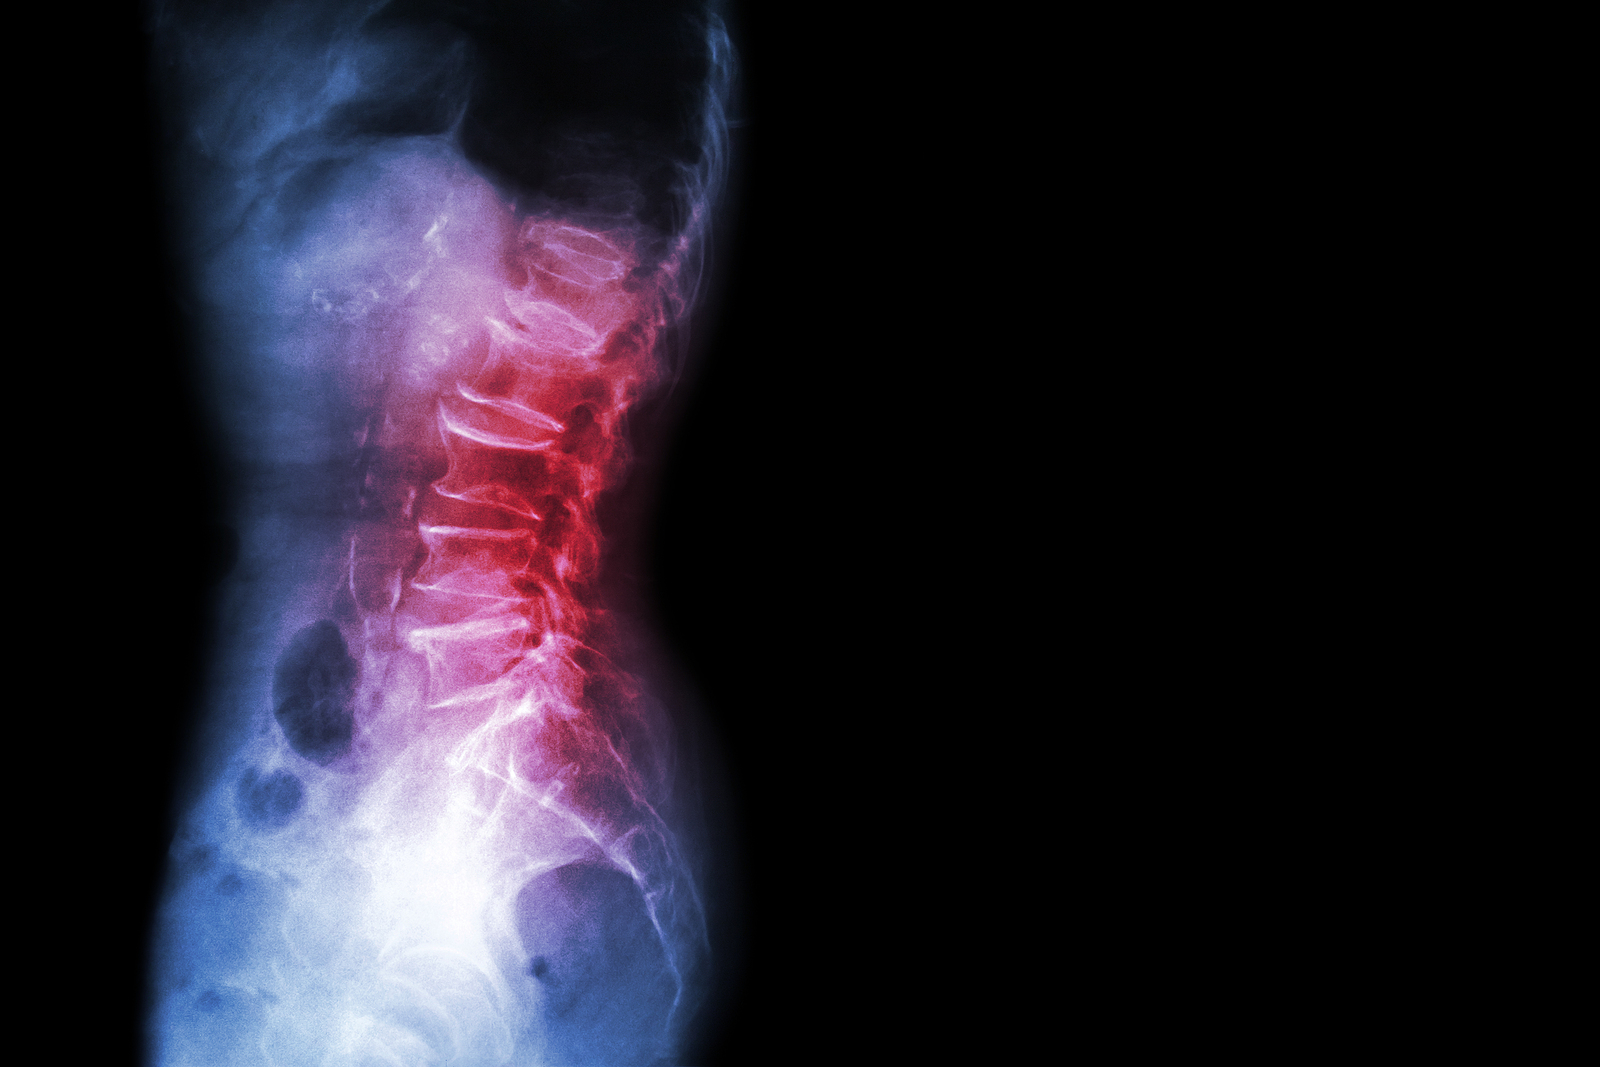

What Makes Up the Lumbar Spine?

The human spine is made up of 24 spinal bones, called vertebrae, as well as the sacrum and the coccyx. The sacrum is a triangular bone near the bottom of the spine and the coccyx is more commonly known as the tailbone.

Vertebrae are stacked on top of one another to create the spinal column. The spinal column gives the body its form and helps sustain an upright position.

The lumbar spine—where pain is often experienced—is made up of five vertebrae positioned near the bottom of the spinal column. Doctors often refer to these vertebrae as levels L1, L2, L3, L4 and L5. The ‘L’ refers to ‘lumbar’. The lowest vertebra, L5, is connected to the top of the sacrum—a triangular bone at the base of the spine that is located between the two pelvic bones. Some people are born with an extra or sixth lumbar vertebra called L6. Having an extra vertebra doesn't usually cause physical problems.